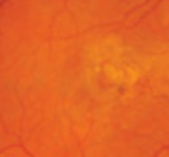

Ocular

Leonid Skorin, Jr., DO, MS, OD

Common eye diseases such as glaucoma, cataract, and age-related macular degeneration can have significant systemic ramifications.